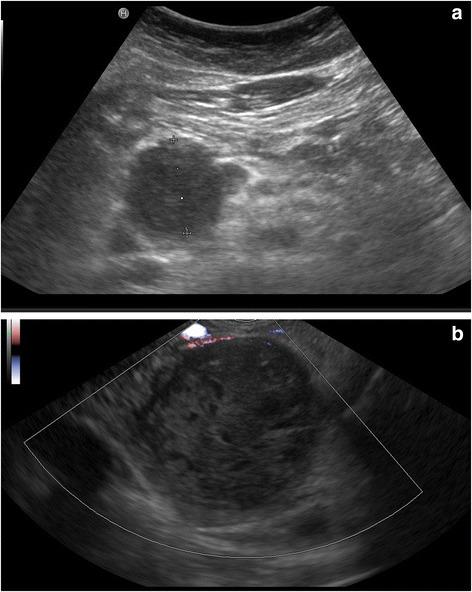

Herein we report the case of an 8 - year old child presenting with symptoms of gastric outlet obstruction.

A solid pseudopapillary neoplasm of the pancreatic caput was diagnosed and surgically removed.

在此我们报告一例8岁儿童出现胃出口梗阻症状的病例。

诊断为胰头实性假乳头状肿瘤并进行了手术切除。